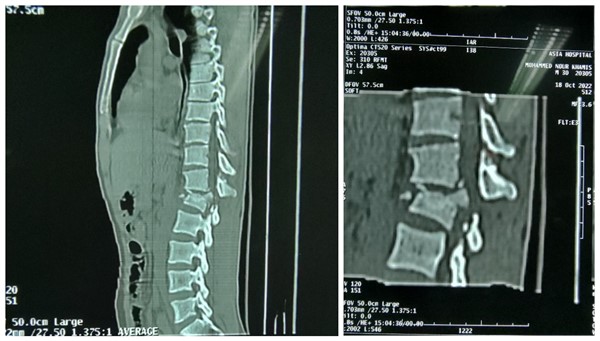

周二一大早,苏丹恩图曼友谊医院骨科门诊就传来了家属急切的声音:“撒艾德 艾黑”,“帮帮我的兄弟”(中文意)。原来是,31岁的法拉赫,一月前不慎从高处坠落,当即出现腰痛,双下肢活动受限,大小便失禁。拍片显示腰1压缩骨折。来自援苏丹医疗队骨科的高宗强副主任医师阅片后和家属详细沟通病情,考虑“腰1压缩骨折伴脊髓受压”,当时就建议手术治疗。因患者家庭经济较紧张,家里一下就丧失了主要劳动力,患者又行动困难,患者及家属多方商议并考虑再三,再次在骨科门诊当面咨询,高宗强副主任医师耐心细致的解答了患者及家属的顾虑,详细讲解了准备实施的手术方案,及可能出现的风险及意外,并与身为骨科大夫的医院院长阿明商议,最大可能的控制手术的费用。病人家属信任的眼神,对手术后康复的急切渴望,这一切都对援苏丹中国医生的肯定。患者入院时,已经是受伤后1月了。入院查体:胸腰段有明显叩击痛,左下肢肌力2级,右下肢肌力3级,双侧足背感觉减退,尿管导尿。

脊髓损伤,在医学领域是世界性难题。一旦损伤,恢复难度很大。所以临床上,一旦出现脊柱骨折造成压迫出现脊髓损伤症状,原则上尽早手术,尽早解除压迫,才有可能更好的帮助神经恢复。但苏丹处于非洲北部,是联合国认定的世界最不发达国家之一,医疗条件相对不足,当地人民经济条件较差。一般病人骨折后,得知需要手术治疗,经过反复考虑,多方筹措住院手术费用,而这,往往已经是几个月后的事情了。这个患者在受伤后一个月住院手术,原则上确实错过了最佳手术时机。但在苏丹当地来说,已经算是治疗相对比较及时了。患者毕竟才31岁,还是家里的顶梁柱,人生的路还很长,还寄托着很多人的希望。做手术还能给脊髓损伤的恢复创造一个良好的条件,如果不做手术,恢复希望渺茫,也许他一辈子就只能与轮椅相伴了。

脊柱骨折钉棒复位内固定术,在我们国内属于常规手术,但在恩图曼医院,尽管骨科是他们的优势学科,以往也只做过1、2例,因此当地医生缺乏相应的手术技巧和经验。而且患者骨折1个月,已经属于陈旧性脊柱骨折,这一切都造成术中复位难度大大增加。而且,神经损伤压迫时间越长,术后效果恢复越差。这里患者的手术治疗及术后恢复实际困难很多,对我们中国医生的技术及心理都造成了一定的压力和挑战。但我们援苏医疗队来苏丹,就是来进行医疗援助,就是想把中国先进的医疗技术和理念传授给他们,更好的服务于苏丹人民,解决当地人民的实际困难,这正是我们此行的使命与担当。来自援苏丹医疗队的骨科团队,高宗强、时亮副主任医师等,立即联系再次看望病人,详细查体,了解病情变化,并与当地恩图曼友谊医院阿明院长及骨科助理huda反复沟通,商谈病情详细制定了第二天手术的方案、所需要使用的器械及可能的预案,尽力做好相关准备工作。